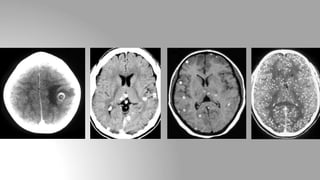

Neurocysticercosis

Stage of the disease CT finding

Vesicular stage Non-enhancing cyst

Colloidal stage Cyst wall enhancement in form of ring

Granular nodular stage Isodense cyst with calcified scolex

Calcified stage Small calcified nodule